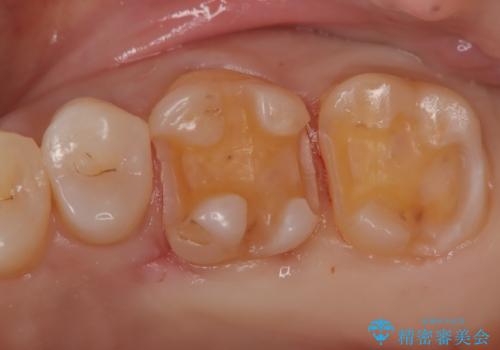

【メタルフリー】セラミックインレーの修復

- メタルフリーを希望された患者さんです。

金属を除去し虫歯の処置をしたあとセラミックインレーにて修復しました。